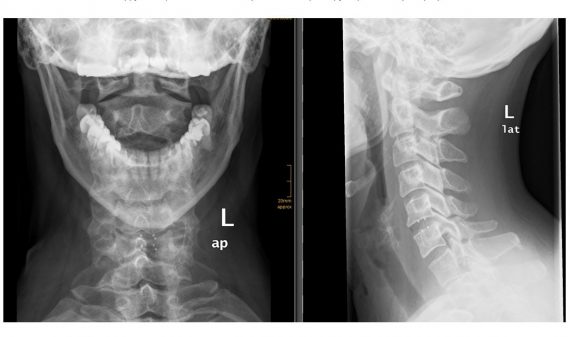

Η αντικατάσταση του αυχενικού δίσκου είναι μια τεχνική που πραγματοποιείται στην αυχενική μοίρα της σπονδυλικής στήλης (αυχένα), και οποία χρησιμοποιείται για τη θεραπεία καταστάσεων η δισκοκήλη. Σε μερικές περιπτώσεις μπορεί να τοποθετηθεί τεχνητός δίσκος και στην οσφυϊκή μοίρα.

Η τοποθέτηση τεχνητού δίσκου έχει σαν στόχο να διατηρήσει την κίνηση των σπονδύλων και να αποτρέψει την εκφύλιση σε άλλα επίπεδα του αυχένα. Η διαδικασία είναι παρόμοια με την κλασσική πρόσθια αυχενική δισκεκτομή (ACDF), ωστόσο, αντί για έναν σταθερό κλωβό, τοποθετείται ένας τεχνητός δίσκος, δηλαδή ένα εμφύτευμα που διατηρεί την κίνηση (Εικόνα 1).